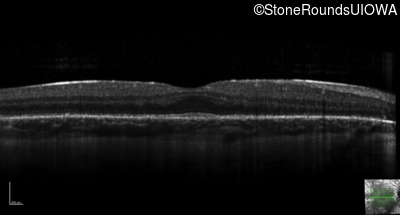

Optical Coherence Tomography - Right - 20/32

Exemplar / OCT Stack